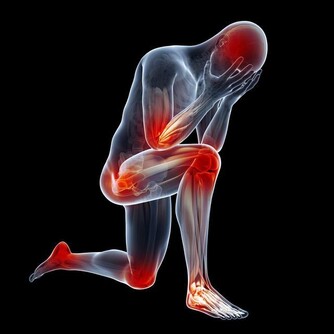

一、腹痛

首先要和大家說的就是,腹痛。這是一種被很多人所忽略的疾病。因為有些人會覺得出現這種情況,只是因為自己吃錯了食物,又或者是冷的東西吃多了,從而刺激腸胃所造成的。並且很多人出現這種情況的時候,身體都能夠自動的分解,比如說,就疼那麼一會兒之後就不痛了。

但是在出現這種情況的時候,就需要你敲響健康的警鐘了。那就是你持續一周到兩周的時間之內,下腹總會有疼痛感,又或者是有下墜感的時候,你就需要非常的小心,因為這有可能是大腸癌的前兆。

而且在你持續性的腹痛時,平常的排便也出現了變化,比如說排便次數明顯的增多,並且有時還會出現血便,並且還會出現便秘。再加上平時體重莫名的開始降低,那麼在這個時候你就需要趕緊去醫院檢查。

很多人由於不明白情況,往往會認為上文中所出現的這種情況,是由於痔瘡又或者是腸炎引起的,從而不去醫院做檢查。

時間一長,就會錯過了最佳的治療時間,從而造成無法挽救的後果。所以大家在平時要是總會腹痛,並且出現上文中所說的這些癥狀的時候,一定要儘早的去做檢查。